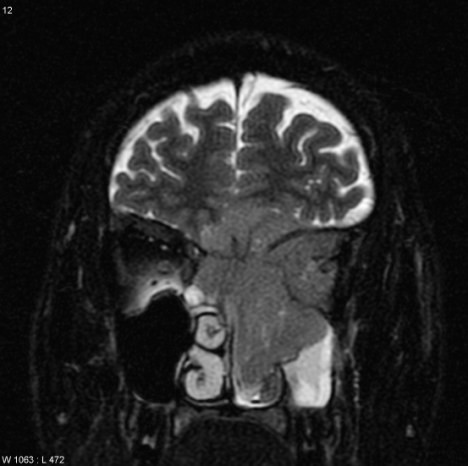

Tumoarea ii crescuse in spatele nasului si ii afecta ochiul stang.

A fost supusa unei alte interventii chirugicale pentru indepartarea tumorii. Lucrurile stateau atat de rau incat medicii au fost nevoiti sa-I reconstituie tot nasul, dar si forma fetei.